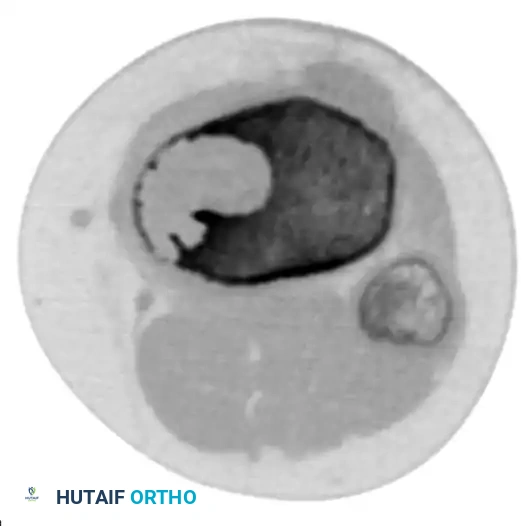

CT scanning is particularly valuable for preoperative planning in areas of complex osseous anatomy, such as the pelvis or spine, to delineate the integrity of the thin cortical rim surrounding the cyst.

Axial CT scan demonstrating the extremely thin rim of remaining cortex overlying the expansile lesion.